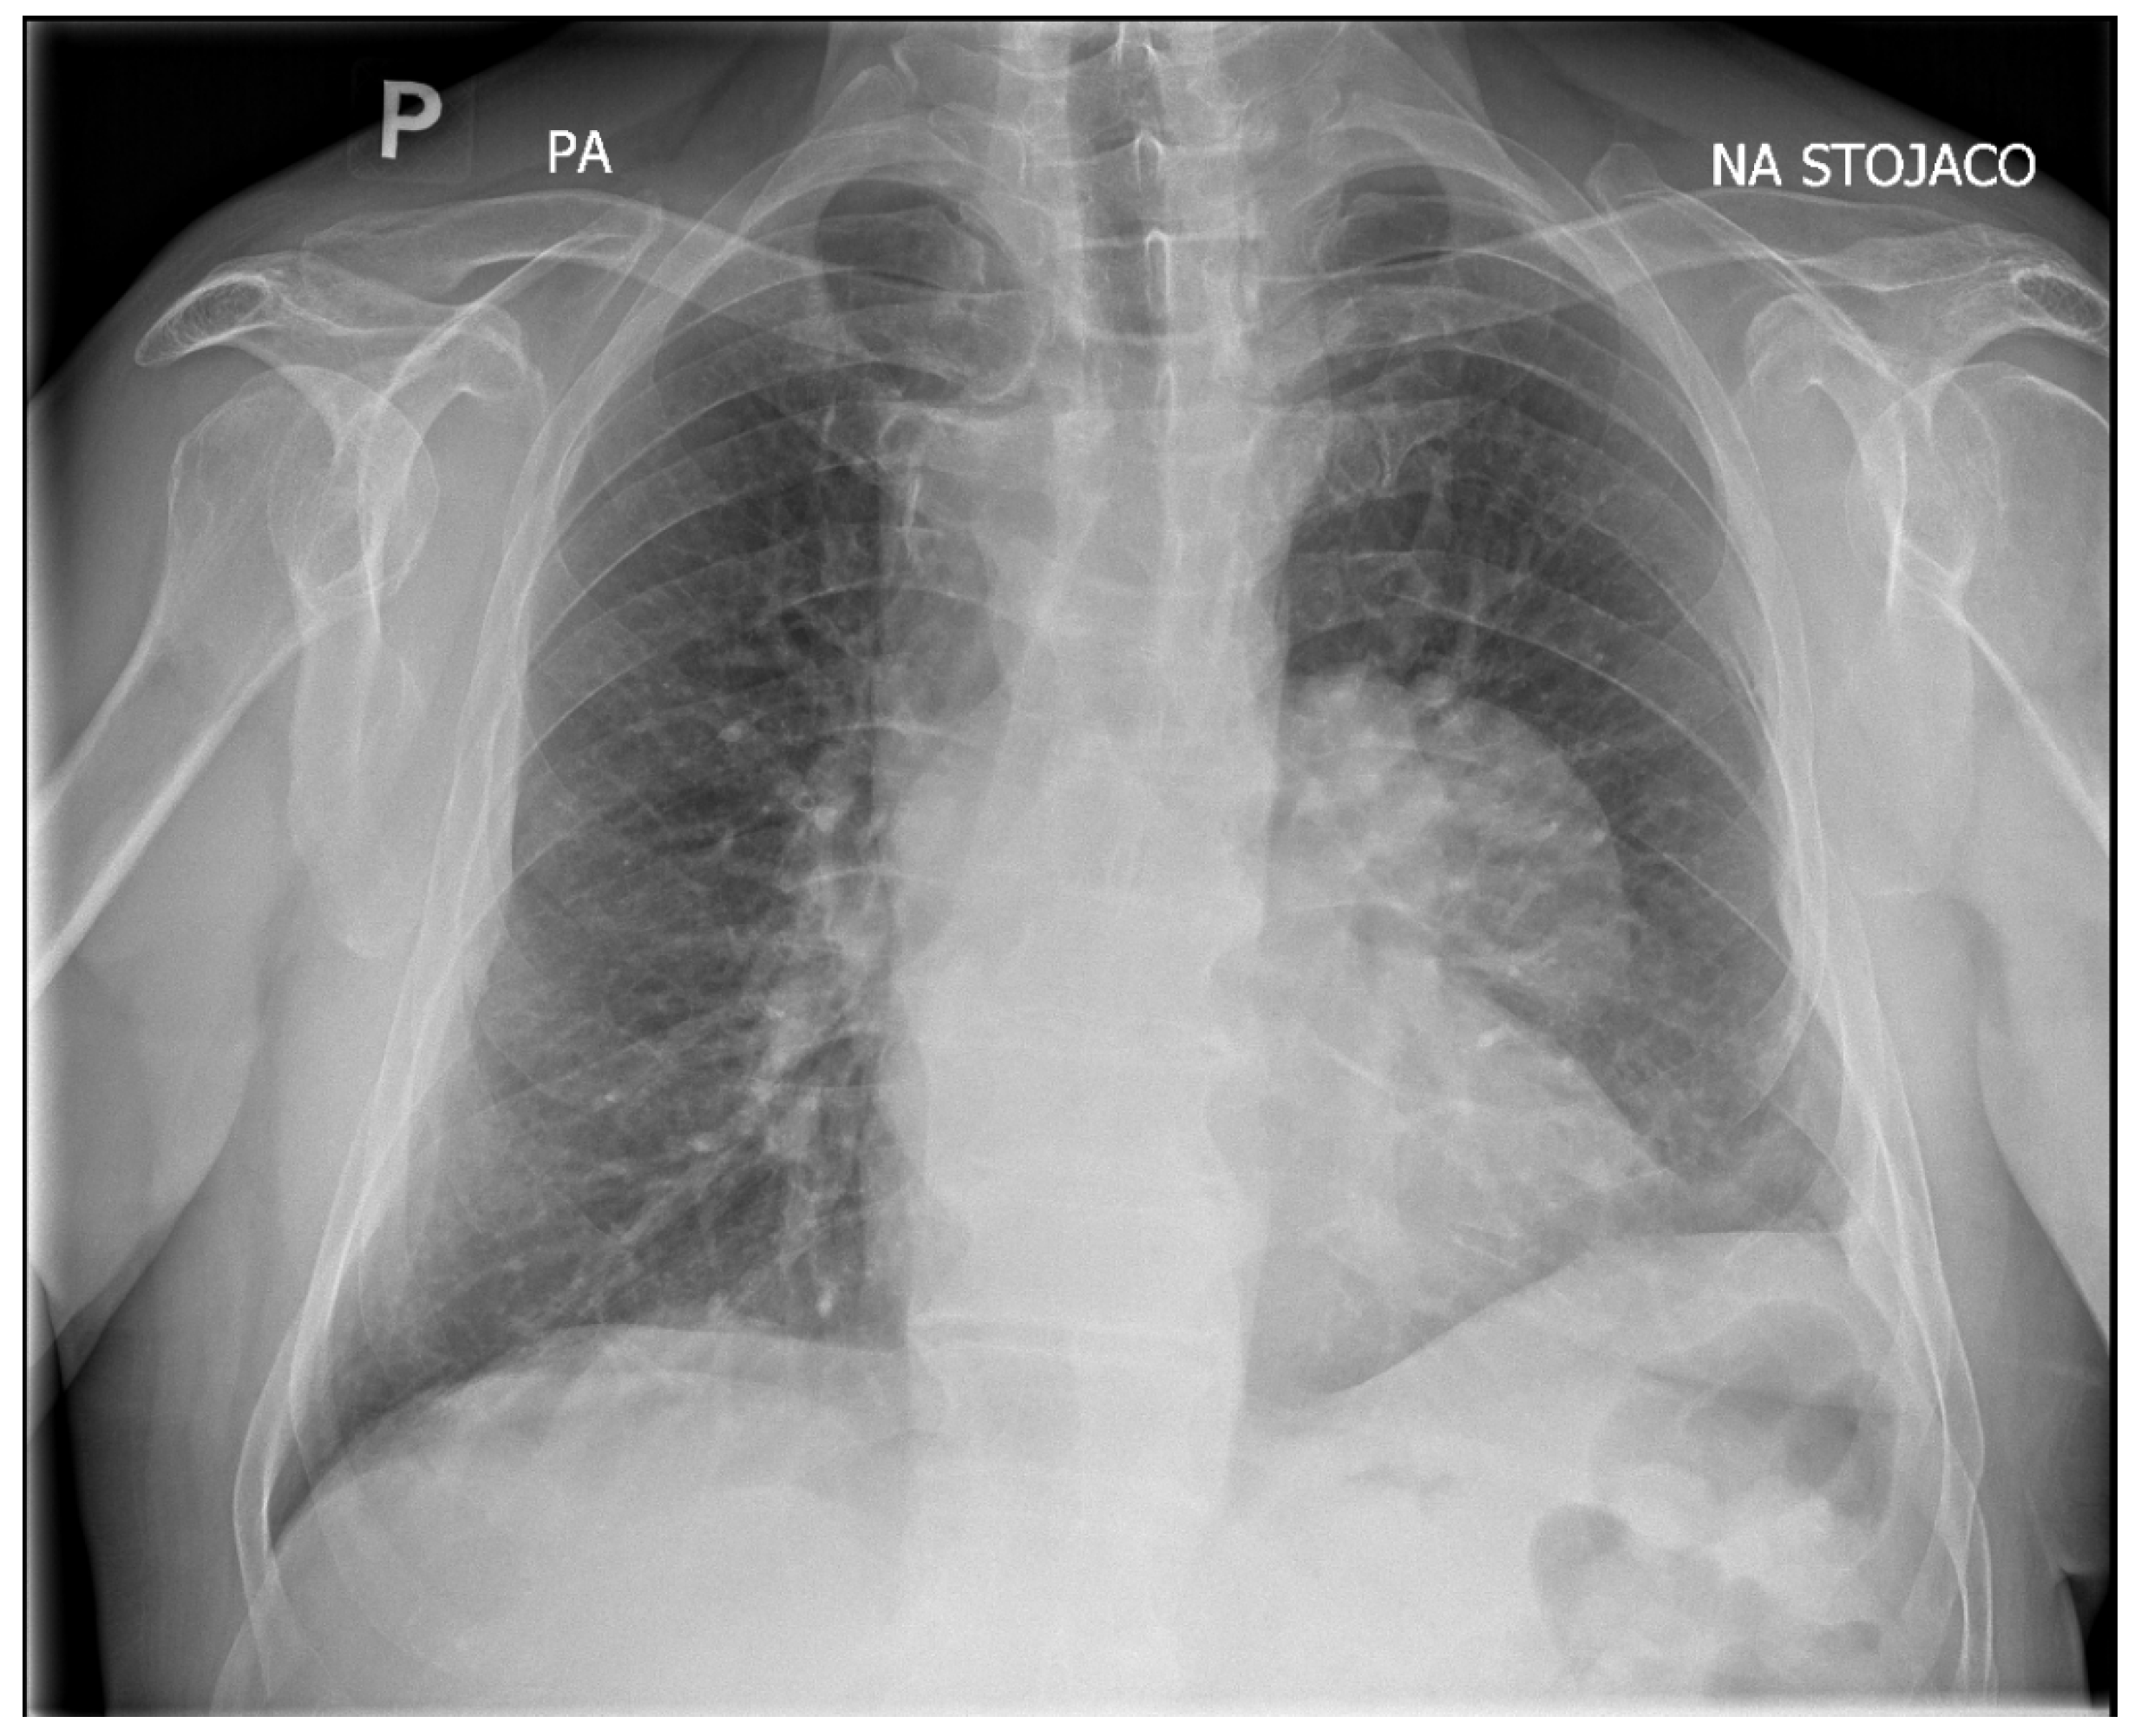

In February 2025, a 69-year-old patient was admitted to the Department of Thoracic Surgery and Transplantology at Pomeranian Medical University in Szczecin for surgical treatment of a mediastinal lesion. Upon admission, the patient reported intermittent chest pain. Chest computed tomography (CT) performed 25 November 2024 had revealed a well-defined, cystic, hypodense lesion in the left anterior mediastinum with an attenuation of 3–7 Hounsfield Units (HU) and measuring (in vivo) approximately 58 mm × 62 mm (axial plane) × 77 mm (long axis) (Figure 1). The cyst walls measured up to 4 mm and had a segmental detached membrane forming thin, flattened pseudo-vesicles (Figure 1). At the upper pole of the cyst, a heterogeneous dense (50 HU) nodular mass exhibited mild contrast enhancement and measured approximately 25 mm in diameter (Figure 1). These findings were equivocal and lacked distinctive features to establish the diagnosis of a pericardial cyst, thymic cyst, hamartoma, or cystic proliferation (lymphoma/meta) of the pericardium or lung. Based on the patient’s history of previous left-sided chest CE and left posterolateral thoracotomy, the differential diagnosis of the mediastinal lesion detected >50 years later should include hydatid cyst.

Upon admission, the patient underwent chest X-ray, which demonstrated well-defined consolidation in the left pulmonary hilum (Figure 2). An echocardiogram revealed that the lesion was not communicating with the heart muscle. However, it was adjacent to the pericardium.

On chest CT, the cyst in the anterior mediastinum of our patient demonstrated features compatible with transitional stages of the WHO-IWGE classification. In this classification, the cyst morphology is visualized using imaging techniques. The detached internal membrane forming flattened pseudo-vesicles corresponds to CE3a (‘water-lily sign’), while the enhancing nodular mass adjacent to the cyst wall suggests a CE3b lesion (Figure 1). According to WHO-IWGE, CE3a and CE3b are transitional stages, distinct from CE1–CE2 (active unilocular or multivesicular cysts) and CE4–CE5 (inactive, degenerative, or calcified cysts). We emphasize that these assignments were derived solely from imaging evidence. Histopathology confirmed echinococcal infection but does not provide staging information.

Figure 1. CT imaging of a cyst in the left anterior mediastinum. (a) Axial chest CT images in the lung window without contrast enhancement. (b) Contrast-enhanced axial chest CT images with the long axis measurement. (c) Contrast-enhanced coronal chest CT images with delineation of its long axis measurement. (d) Focal detachment of the cyst’s internal wall – indicated by the arrow. (e) Contrast-enhanced nodular mass adjacent to the fluid-filled cyst – indicated by the arrow.